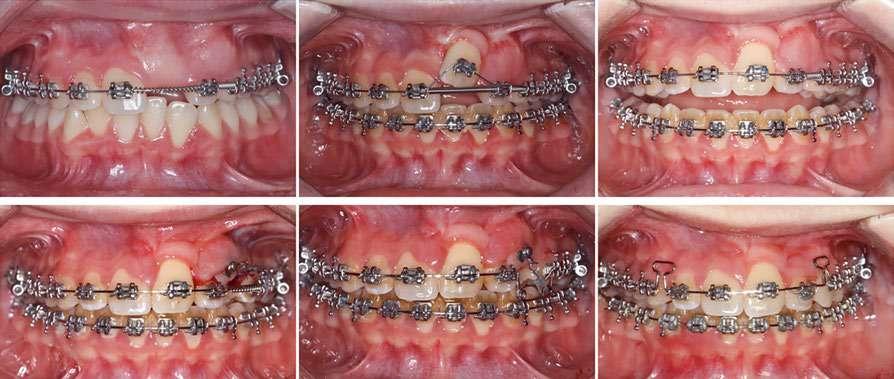

Este artículo de revisión evalúa el manejo de la impactación de los caninos permanentes maxilares. Esta alteración presenta una etiología multifactorial y es la impactación más frecuente después de la de los terceros molares. Para llevar a cabo un correcto tratamiento es necesario un exhaustivo estudio clínico y radiográfico. El tratamiento de los caninos incluidos es ortodóncico-quirúrgico y se realiza en tres fases: ortodoncia prequirúrgica, cirugía de acceso al canino y ortodoncia posquirúrgica.

La impactación de los caninos permanentes superiores es la segunda forma más común de impactación de dientes después de los terceros molares, siendo dos veces más común en mujeres que en hombres (Becker y cols. 2015). La erupción del canino permanente suele ocurrir alrededor de los 11 años, por lo que la sospecha de su inclusión suele comenzar a los 14-15 años. La impactación palatina es más frecuente que la impactación vestibular (3 veces) y la unilateral más común que la bilateral (Chung y cols. 2011). La etiología es multifactorial y podría estar relacionada, entre otras causas, con discrepancias en el tamaño del diente y la longitud de arcada, genética, erupción tardía, deficiencia transversal del maxilar, migración dentaria, traumatismo en el maxilar o agenesia/anomalía de posición en incisivo lateral (Martínez Madero y cols. 2022; McConnell y cols. 1996).

Clínicamente, los caninos incluidos se caracterizan por la erupción retardada del canino permanente, la erupción asimétrica de ambos caninos, la ausencia de protuberancia canina en el fondo de vestíbulo o presencia de protuberancia palatina en la región canina, el retraso en la erupción o migración distal de incisivos laterales permanentes, la retención prolongada de canino temporal sin movilidad y pérdida de vitalidad o el aumento de movilidad de incisivos permanentes (Mason y cols. 2001).

El diagnóstico radiográfico en dos dimensiones de un canino incluido se lleva a cabo mediante la radiografía periapical con la técnica de Clark y la radio-

grafía panorámica. En esta última, se han estudiado diferentes variables radiográficas para la evaluación del pronóstico de los caninos incluidos. En 1988, Ericsol y Kurol establecieron cinco sectores según los ejes longitudinales del incisivo central y lateral y líneas paralelas que pasan por los puntos de contacto desde el incisivo central al primer premolar. Así, describieron métodos para conocer la posición mesio-distal de la corona del canino, la inclinación del mismo respecto a la línea media y al incisivo lateral y el grado de predictibilidad de la erupción del canino, siendo un peor pronóstico cuando más a mesial se encuentre su cúspide. Se determinó también el ángulo alfa definido por el eje longitudinal del canino con la línea media y se consideró un valor normal, con buena predictibilidad de erupción, un ángulo de 25º (Ericson y Kurol 1986, 1988) (Figura 1). McSherry (1996) describió “la regla vertical de los tercios”. Con ello, se puede esperar un buen pronóstico si la punta de la cúspide canina está al nivel de la unión amelocementaria del incisivo adyacente, mientras que un canino con mal pronóstico para la alineación sería aquel en el que la punta de la cúspide estuviera contra el tercio apical del incisivo adyacente (McSherry, 1998). Pitt, en el año 2005, evaluó con una puntuación de 1 a 4 el grado de dificultad de alineación del canino incluido en la arcada dentaria teniendo en cuenta su altura vertical, posición horizontal respecto al incisivo lateral, posición vestíbulo-palatina y la edad del paciente (Pitt y cols. 2006).

Actualmente, la tomografía computarizada de haz cónico (CBCT por sus siglas en inglés: Cone Beam Computed Tomography) y la reconstrucción 3D nos permiten ver con más claridad la posición del canino y su relación con estructuras adyacentes (Alqerban y cols. 2009). En el año 2000 se desarrolló un nuevo método para evaluar, a partir del CBCT, la dificultad prevista para posicionar un canino incluido, el índice KPG. Este índice clasifica la posición del canino en función de su distancia de la norma, dando un número en una escala de 0 a 5 tanto para la

Figura 1. Diagnóstico clínico y radiográfico de un caso de inclusión de caninos. a) Cementado de brackets; b) Corte coronal del CBCT: inclusión por palatino de 1.3 y 2.3; c) Arcada con espacio preparado para caninos mediante coils abiertos; d) Radiografía panorámica: pronóstico

2.3 según

cúspide como para la punta de la raíz. La suma de las seis puntuaciones obtenidas evalúa la dificultad prevista del canino (Dalessandri y cols. 2013).

En relación con el tratamiento de este tipo de inclusiones dentarias, la literatura refiere que la extracción del canino temporal como tratamiento interceptivo es beneficiosa para la erupción espontánea del canino incluido, siempre y cuando tenga una posición y distancia favorables respecto al plano oclusal (Ahlam y cols. 2023; Almasoud 2017; Benson y cols. 2021). Debido a la etiología mencionada, es necesario conseguir espacio suficiente para favorecer la erupción del canino retenido en aquellos casos que no lo tenga, con aparatología fija multibrackets o alineadores. En otros casos, la expansión rápida del maxilar y la posterior colocación de una barra transpalatina, seguidas de la extracción del canino deciduo, son opciones de tratamiento interceptivo eficaces para pacientes de 9 a 13 años que presentan caninos palatalmente desplazados (Baccetti y cols. 2011).